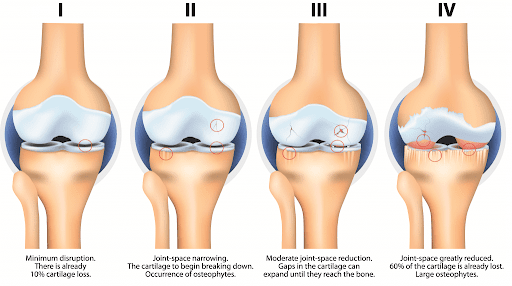

الف:استئوآرتریت(بیماری استحاله ای مفصلی):واژه استئو ارتریت (ارتروز)منحصرا به از بین رفتن و تخریب شدید غضروف مفصلی اشاره دارد این عارضه ممکن است اولیه یا ثانویه داشته باشد دلیل ارتروز اولیه مشخص نیس ولی در بیشتر زنان دیابتی شایع است چاقی علل به وجود اورنده ی این بیماری نیست ولی پس از شروع موجب تسریع در روند آسیب می شود ولی ارتروز ثانویه بعد از اسیب مفصلی و بیماری مفصلی به وجود می اید –شکستگی سطوح مفصلی –اسیب دیدگی رباط ها-دررفتگی ها–عفونت و رماتیسم مفصلی –واردآمدن نامناسب نیرو به مفصل –بالا رفتن سن.دلالیل ارتروز ثانویه می باشد (در عکس الف و ب مشاهده کنید )

تغییرات پاتولوژیک مفصل در بیماری آرتروز:آرتروز چه اولیه باشد چه ثانویه تغییرات مفصلی ناشی از ان یکسان خواهد بود ابتدا غضروف مفصلی نرم _و به دنبال آن سطح ناهموار می شود _غضروف ساییدگی می یابد_شکاف و ترک ها بیشتر می شود و به سمت پایین وزیر استخوان گسترش می یابدودر نهایت غضروف به کنار می رود سطح استخوان اشکار می شود و همین سطح عهده دار تحمل وزن وارده بر مفصل است سفتی استخوان یا (اسکلروسیس)و بخش های پایین (کیست ها )به طور همزمان تشکیل می شوند ودر نتیجه ضخیم شدن کپسول مفصلی استحاله های استخوانی (استئوفیت)شکل می گیرند .

عکس (الف)